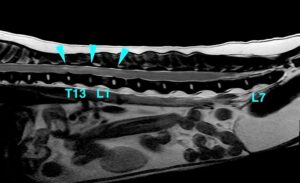

脊髄の一部が白く変色(青矢頭)これは脊髄の炎症・浮腫・出血などを表しており、「線維軟骨塞栓症」が疑われた